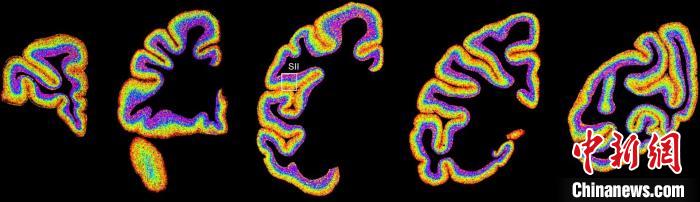

圖為不同類(lèi)型細(xì)胞在獼猴大腦上的分布切片。 中國(guó)科學(xué)院腦科學(xué)與智能技術(shù)卓越創(chuàng)新中心 供圖

李澄宇說(shuō),科研人員做的事情好似“查戶(hù)口”,也就是搞明白猴腦里有哪些細(xì)胞、這些細(xì)胞在哪些位置。搞明白這些就形成了一個(gè)大的數(shù)據(jù)集,科研團(tuán)隊(duì)挖掘這個(gè)數(shù)據(jù)集,發(fā)現(xiàn)了很多有意思的現(xiàn)象:比如,興奮性神經(jīng)元、抑制性神經(jīng)元以及非神經(jīng)元在大腦皮層中的分布呈現(xiàn)明顯的特異性,也就是不同細(xì)胞“住”哪,有一定規(guī)律。